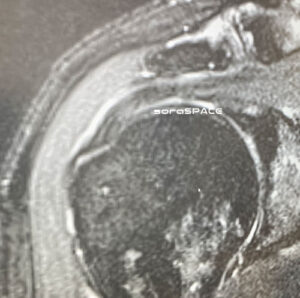

レントゲンを撮った結果

肩峰下インピンジメント症候群とのこと

腱はこの時点では若干傷があるかもしれない・・

私の場合は中を見てみて腱を確認し必要であれば腱も縫うとのことで

これがされると肩の固定期間も長くなりますし、無ければ翌日には腕は自由になると

インピンジメント症候群の術後聞いたのは

腱は傷が少しある程度なので処置なし